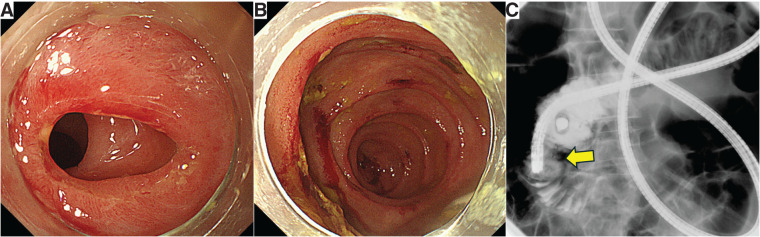

Introduction: Primary gastrointestinal follicular lymphoma (FL) rarely causes intestinal stricture. We report two cases of small intestinal FL presenting with stricture.

Case presentation: Case 1: A 63-year-old man presented with small intestinal obstruction. CT demonstrated ileal wall thickening and enlarged lymph nodes. Partial ileal resection confirmed primary ileal FL, immunohistochemically positive for CD10, CD20, and BCL-2. Case 2: A 79-year-old woman with a 7-year history of jejunal strictures underwent right hemicolectomy for ascending colon cancer and partial jejunal resection. Pathologic examination showed concurrent jejunal FL and colon adenocarcinoma. Immunohistochemical findings were the same as in Case 1. In both patients, postoperative positron-emission tomography-CT showed no residual lymphoma. Both were monitored clinically without chemotherapy.